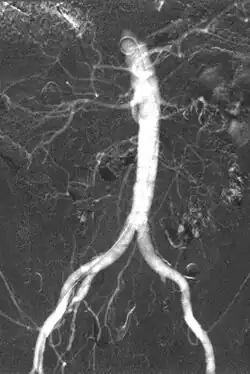

A CO2 angiogram showing abdominal aorta, visceral arteries and iliac arteries

Carbon dioxide also has a role in angioplasty. It is low-risk as it is a natural product with no risk of allergic potential. However, it can be used only below the diaphragm as there is a risk of embolism in neurovascular procedures. It must be used carefully to avoid contamination with room air when injected. It is a negative contrast agent in that it displaces blood when injected intravascularly.